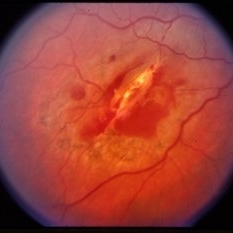

Pre-retinal and retinal hemorrhage.

Condition/keywords: retinal hemorrhage, trauma